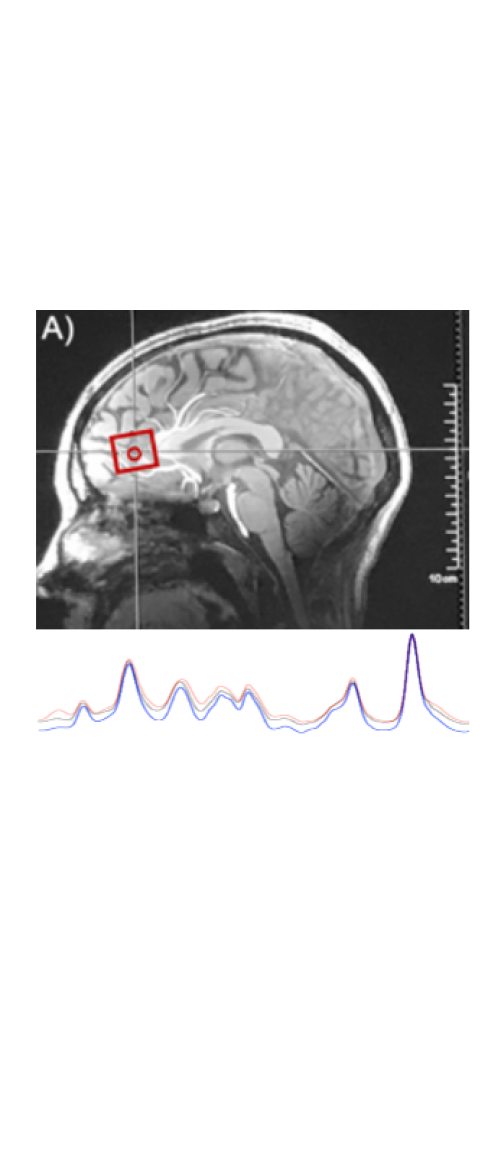

We developed a novel method for imaging the effect of ketone bodies on the human brain. Using a series of neuroimaging techniques, including fMRI at various teslas and MR spectroscopy, and subsequent analyses on the data derived from these scans, we are able to image and quantify the action of ketones in the brain.

Ketones (beta-hydroxybutyrate) increase Gibbs free energy by ~27% as compared to calorie-matched glucose. Here, using 7T fMRI, we investigate the impact of increased energy on the brain, even in younger adults.